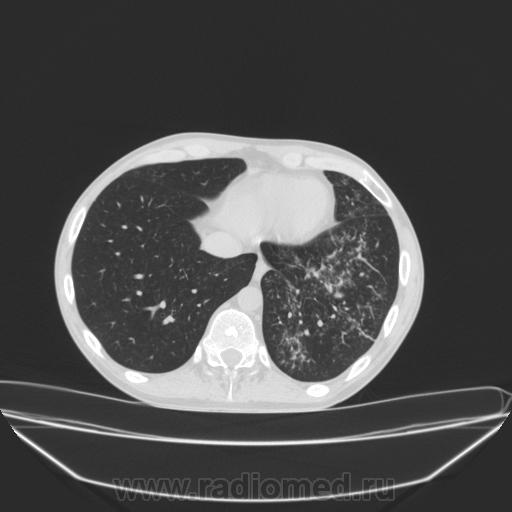

Добрый день, коллеги!  Больной поступил в стационар  с обильным носовым кровотечением, обследован  ОКГ- деструктивная пневмония слева. Пролечен в течение 3 недель, направлен после 2го рентгенконтроля на КТ дообследование. Классический тбс. Помогите описать эту классику, плохо ориентируюсь в КТ терминологии.

Если по терминам: общее - отмечаются участки уплотнения легочной ткани; отдельные - консолидация (это как инфильтрация но только по катэшному_, полости распада (если выделываться, то кавитация), внутридольковые (центрилобулярные) уплотнения/плотности/очаги с неровными, нечеткими внешними контурами.

Если подробнее - нужны дайкомы.